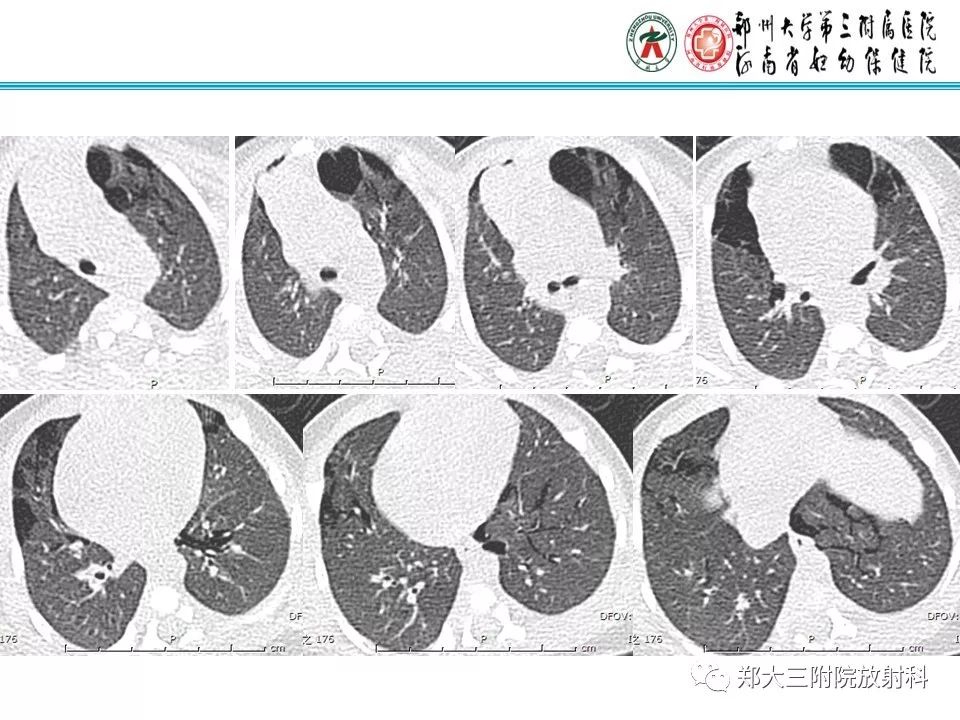

间质性肺气肿的影像诊断